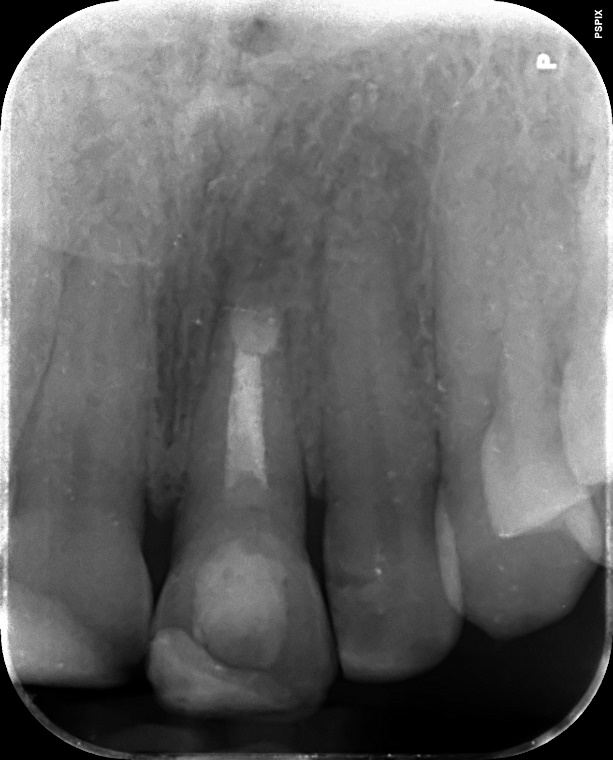

Upper Incisor trauma case primary root canal treatment and rebuild